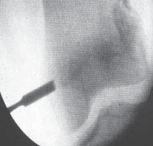

2. Under image intensification control, the curette is rotated and advanced to the level of the inner third of the physis (

TECH FIG 2B

).

3. The curette is then swept cephalad and caudad in the physis to ablate the peripheral third of the physis, leaving the middle third intact (

TECH FIG 2C

5. Specific surgical attention is directed toward adequate ablation of the most peripheral aspect of the physeal plate (

TECH FIG 2D–F

6. The same operative process is repeated on the opposite side of the physeal plate (medially or laterally), again sparing the middle third of the physeal plate.

--- A B CTECH FIG 2 • A. The curette is advanced through the incision into the hole of the femoral cortex. B. The curette is rotated and advanced to the level of the inner third of the physis. C. The anticipated area of ablation of the peripheral third of the physis (both medially and laterally). The curette is swept cephalad and caudad in the physis to ablate the peripheral third of the physis, leaving the middle third of the physis intact.